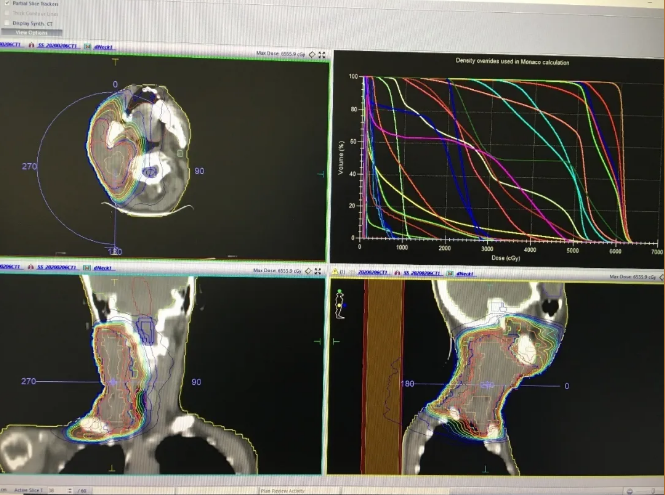

第四步:物理计划制定与评估

此部分由物理师来完成,最终由医生和物理师共同确认该计划是否可行。

第五步:计划验证

此部分由物理师完成,确认该计划实际剂量分布与计划系统计算的剂量是否吻合,误差过大,需要找出原因,甚至需要重新制定放疗计划。

整个过程中,需要医生、物理师和技师各司其责,密切配合。一般的放疗计划常常需要1-2天时间才能完成,复杂的计划甚至需要一周的时间去不断优化。

北京燕化医院放疗科安装有GE大孔径CT和医科达高端直线加速器Infinity,可做三维适形放疗、普通调强放疗、旋转调强放疗(VMAT),同时配备图像引导技术及六维床,是目前世界上较先进的直线加速器。